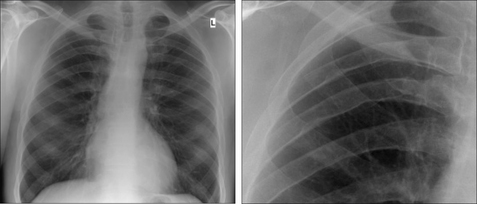

image

Figure 31.7 Adult. Coarctation. The main finding is the posterior and inferior rib notching. The mediastinum demonstrates a (somewhat) high knuckle appearance.